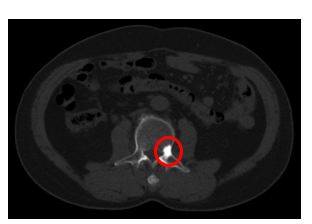

Hình 2: Hình ảnh Cắt lớp vi tính ổ bụng có nốt đặc xương bờ sau thân đốt sống L3 (mới xuất hiện so với trước đây).